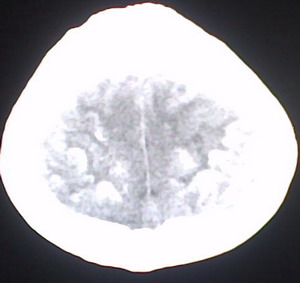

以下是引用jiajie在2009-2-3 20:02:00的发言:[br]脑室周围白质区可见大量斑片状钙化,部分融合成带状,双侧侧脑室及第三脑室扩大。[br]考虑弓形体原虫感染。(先天性宫内感染、torch综合症)

以下是引用lkc8963在2009-2-3 21:15:00的发言:[br]临床眼睑可见静脉扩张,ct双侧眼上静脉亦示扩张,颅内钙化以皮层\\软脑膜为主而不是位于白质和室管膜,再加上静脉窦异常,还是应该考虑静脉血管瘤病,可能为较复杂的血管畸形.

以下是引用卜一在2009-2-4 9:21:00的发言:[br]sturge-weber综合征:面部三叉神经分布区的毛细血管性或海绵状血管瘤以及同侧枕、顶或额叶软脑膜的血管瘤(以静脉性为主)。脑皮质,特别是第二三层,毛细血管可有增厚和钙化。局部发生层状坏死、神经细胞脱失、萎缩、胶质细胞增生及钙盐沉着。可根据面部典型分布的特征性皮痣作出诊断。头颅ct:发现面部血管瘤同侧的脑内病理钙化影,呈双层线条波浪形、脑回形或树枝形。本例支持:sturge-weber综合征![br]